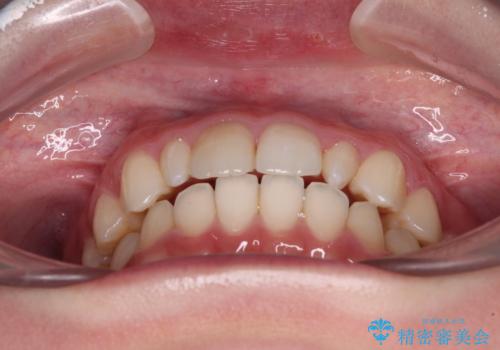

- 歯列のデコボコを気にして来院された患者様です。

安価に速やかに治療をしたいとのことで、メタルワイヤーにより矯正治療を行うこととしました。

上顎左右側切歯は矮小歯であり、矯正治療開始前にオールセラミッククラウンによる形態修正を兼ねた補綴治療を提案しましたが、特に気にならないとのことで、歯冠形態はそのままとしました。